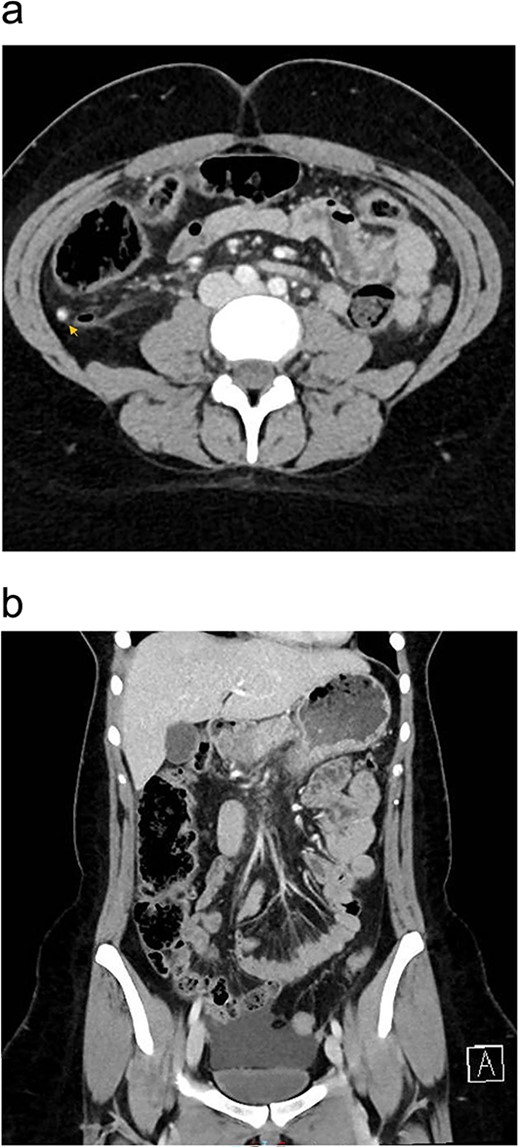

Upon presentation, the patient was vitally stable except for a low-grade fever (37.8°C). Her abdominal examination revealed tenderness in the paraumbilical and right lower quadrant regions with positive rebound and Rovsing signs. Abdominal X-ray was unremarkable. Laboratory investigations revealed leukocytosis (Table 1). Enhanced CT scan of the abdomen and pelvis revealed signs of appendicitis with a moderate amount of free fluid (Fig. 1a and b).

Preoperative enhanced CT abdomen and pelvis with axial (a) and coronal (b) views showing dilated appendix with hyperdense appendicolith within its lumen (arrow) associated with surrounding fat stranding and moderate amount of free fluid of −7 to 0.4 Hounsfield Units density.